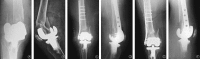

This study was designed to itemize and analyze the classification of fracture types and their corresponding outcomes in an attempt to provide a better understanding of the current treatment methods. Two PubMed searches were performed using the words "periprosthetic distal femur fracture" and "periprosthetic supracondylar femur fracture" in studies that were published in the previous 10 years (2004-2014). Data from 41 articlesthat met the general inclusion criteria, were collected and categorized into fracture type and treatment method groupings. Healing outcome and complications were the two parameters used to analyze the data. Treatment techniques were grouped in the following categories: locking plate, non-locking plate, intramedullary nail/rod, screw, blade plate, cerclage wires, allograft, external fixation, revision arthroplasty, non-operative, and other. Classification systems by Lewis and Rorabeck, the Association for Osteosynthesis/Orthopedic Trauma Association (AO/OTA), Su et al., Neer et al., Kim et al., Backstein et al., and the Société Française de Chirurgie Orthopédique et Traumatologique were reported. In total 448 fractures were identified, of which Rorabeck type II was the most common fracture studied. The two most successful treatment options for periprosthetic distal femur fractures were locking plate (87%) and intramedullary nail/rod (84%). The most frequent complications associated with periprosthetic distal femur fractures included non/mal/delayed union and the need for revision. Locking plates used to treat Rorabeck type II fractures had a complication rate of 35% and those treated with intramedullary nailing had a higher complication rate of 53%. In conclusion, the most frequent type of periprosthetic distal femur fracture after total knee arthroplasty was Rorabeck type II. The most common treatments for these types of fractures are locked plating and intramedullary nailing, with similar healing rates of 87% and 84%, respectively. However, the complication rate for locked plating was lower than for intramedullary nailing.